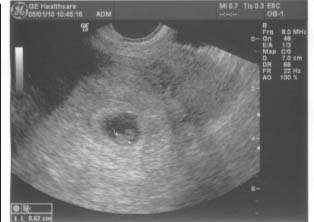

Ma reggel 9re mentem, felküldtek uh-ra!

felfeküdtem az ágyra a genetikain - állítólag az a jobb gép - és az uh dokin láttam hogy ráncolja a szemöldökét! Mondtam neki, hogy: Ja, ketten vannak...bocsánat elfelejtettem mondani!

Mire közölte, hogy nem, nem ketten vannak!

na ott egy pillanatra megállt a szívem, hogy te jó ég, mi történt a babával, vagy a babákkal!

mire rám nézett,és közölte, hogy nem, nem ketten...hárman vannak!

mondtam, hogy háááááárman????????????

mondta hogy ha nem hiszem, a szememnek már csak elhiszem.... és megmutatta külön mindhármukat és a szívhangokat is

mire átsétáltam azon a 20 méteren, már át is telefonált, és mentem be Konc doktorhoz... megvizsgált pocak uh-n is és hüvelyin is.... bizony, a kettő beültetett babciból az egyik tovább osztódott...

Ma megnéztem őket egyenként, teljes monitor nagyságban..... jajjjj Lányok! forgatják a fejüket, és folyamatosan kalimpálnak a kezeikkel, lábaikkal.... olyan gyönyörűek..... az egypetéjűek 36 és 37 mm-esek, a külön petezsákban lévő babócka 38 mm!

állítólag azért nem lehetett látni még legutóbb - 7 hetes uhn - mert akkor elbújt a kis huncut a másik mögé!